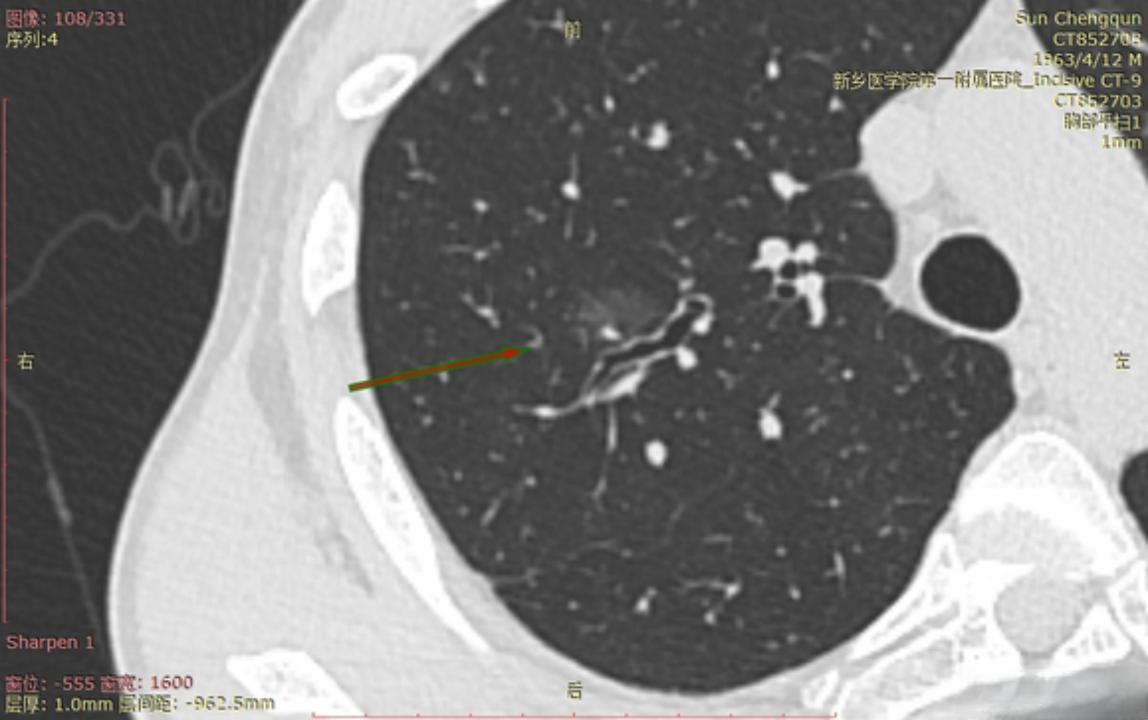

多发磨玻璃结节渐显高危因素,少数已癌变,如何手术治愈?

多发磨玻璃结节(GGN)是一种常见的肺部影像学表现,通常在高分辨率计算机断层扫描(HRCT)筛查中被发现。近年来,随着肺癌筛查项目的开展,多发GGN的诊断越来越频繁,大约20%-30%切除的GGN病变伴有其他多发较小的肺内GGN病变。

多发GGN的恶性概率不容忽视。研究发现,GGN大小与肺癌存在相关性,6 mm-10 mm的恶性概率为20%,11 mm-20 mm的恶性概率为45%。此外,GGN在随访期间大约有20%-30%的概率进展,多是原位腺癌(AIS),很少有浸润性腺癌。这些数据表明,多发GGN存在一定的癌变风险,需要引起重视。